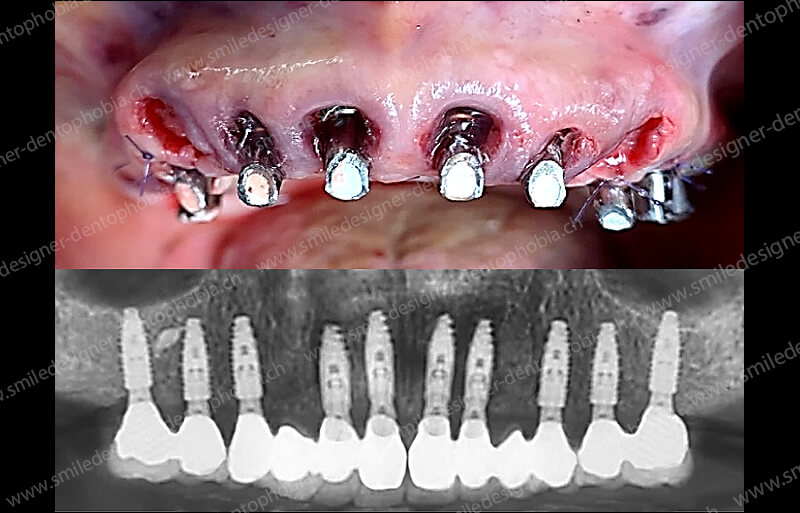

Cas clinique « GOLD STANDARD MCI » maxillaire : Bridge implanto-porté sans extension (ALL ON 8). Version définitive des bridges avec un cosmétique en céramique.

Cas clinique « GOLD STANDARD MCI » maxillaire : Bridge implanto-porté sans extension (ALL ON 10). Version définitive des bridges avec un cosmétique en céramique.